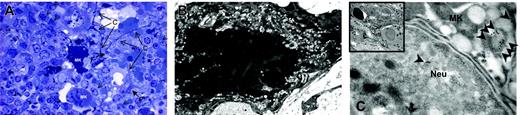

TPO treatment had profound effects on the morphology of Mks both in wild-type and GATA-1low mice. In wild-type mice, the overall morphology of the Mks in the spleen became less mature, as revealed by reduced localization of P-selectin (Schmitt et al32 and results not shown) and von Willebrand factor (Table 2) on the α-granules. In addition, a significant portion (31 ± 2.6%) of these Mks had the heavy-electron dense para-apoptotic morphology originally described for GATA-1low Mks22 and contained neutrophils embedded in the cytoplasm, as confirmed by myeloperoxidase immunostaining (Figure 4). In contrast, in TPO-treated GATA-1low mice, the morphology of the Mks became more mature with clearly delineated platelet territories and significant increase, both in number and in localization to the α-granules, of von Willebrand factor–related gold particles (Figure 5; Table 2). These stage III Mks, never detected in untreated mutants,22 represented 28.5% of the Mks in spleen from TPO-treated GATA-1low Mks.

The Mks in the spleen from TPO-treated wild-type mice expressed several morphologic abnormalities characteristic of GATA-1low Mks. Semithin (A) and ultrathin (B-C) sections of the spleen from TPO-treated wild-type mice. The semithin section (A) shows a cluster of light- and heavy-electron dense Mks (Mk) surrounded by numerous neutrophils (arrowheads), fibroblasts (F plus arrows), and connectival fibers (CF). Upon ultrastructural examination (B), heavy-electron dense Mks present a morphology of cytoplasm and nucleus compatible with that of cells undergoing para-apoptosis.22 Furthermore, heavy-electron dense Mks contain neutrophils (Neu) embedded in their cytoplasm (insert in C), as proved by immunogold staining for myeloperoxidase (C) that shows gold particles (arrowheads) in the cytoplasm both of the neutrophil and of the Mks. Similar results were observed in the spleen of at least 3 separate TPO-treated wild-type mice. Magnification: × 100 (A), × 3000 (B, insert in C), and × 30 000 (C). Numerical aperture of the objective lenses: 0.1.